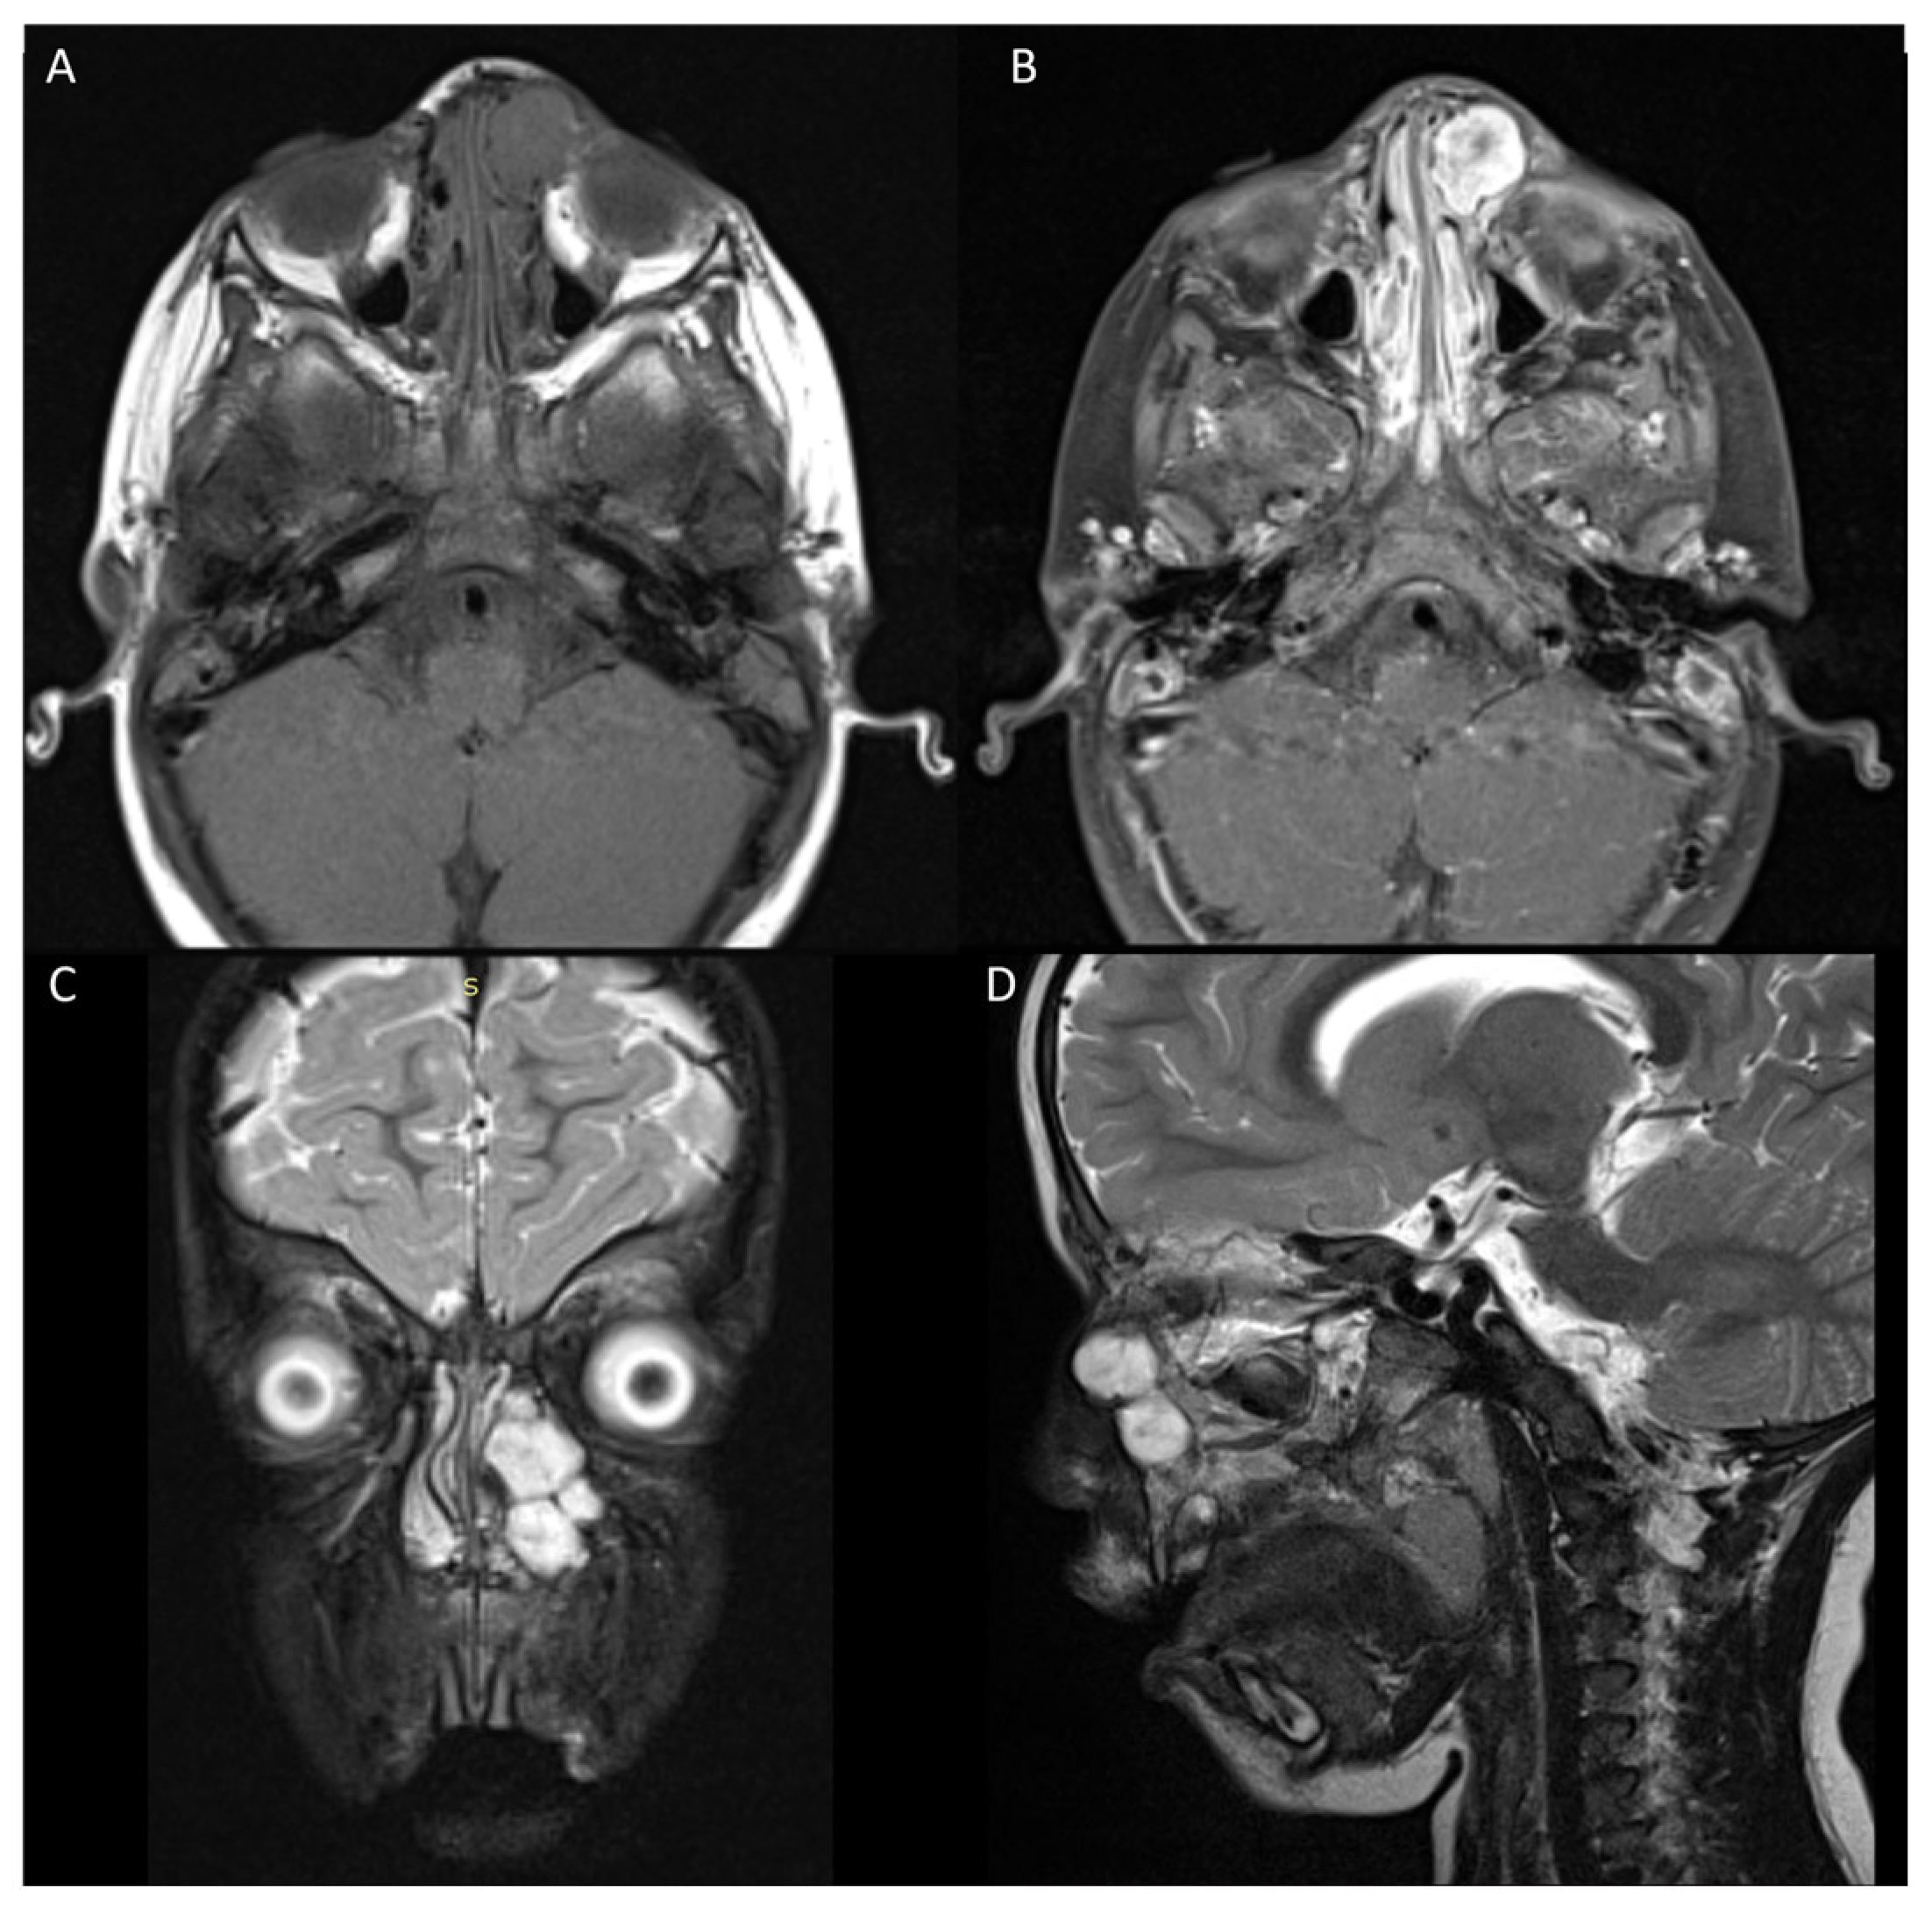

3.2. Case 2